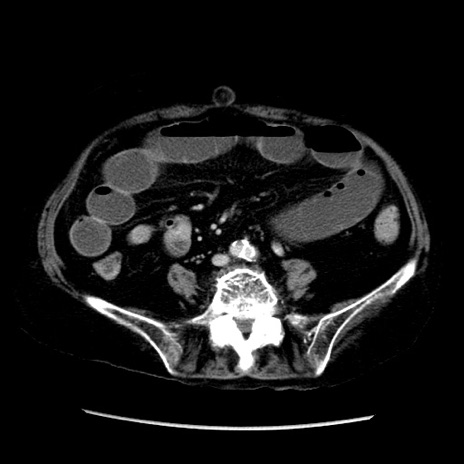

冠状断像

症例14(横断像)

【症例】 90歳代女性

【主訴】 腹痛・嘔吐

【現病歴】今朝から左側腹部痛を認めた。 経過観察していたが、嘔吐を認めたため来院。

【既往歴】 子宮癌術後

【身体所見】 意識清明、BP 127/54mmHg、P 98bpm Sp02 95%(RA)、BT 35.8°C、腹部平坦・軟腸ぜん動音聴取良好、右下腹部圧痛(+) 反跳痛なし

【データ】WBC 9800、CRP 0.46